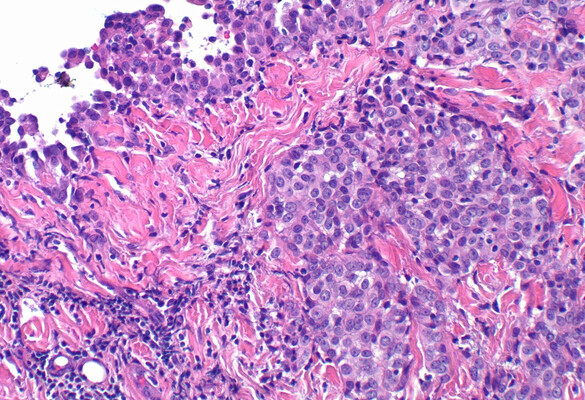

Mesothelioma is an asbestos-associated malignant form of cancer, which often has a poor prognosis in humans after disease onset.

- The current invention describes an immune-oncolytic method by combining intratumoral administration of oncolytic modified vaccinia Tian Tan (MVTT) virus and depletion of myeloid-derived immunosuppressive cells (MDSCs) to induce protective T cell immune responses that exhibited dose-dependent effects in regression of solid tumors such as mesothelioma (AB1) and melanoma (B16F10).